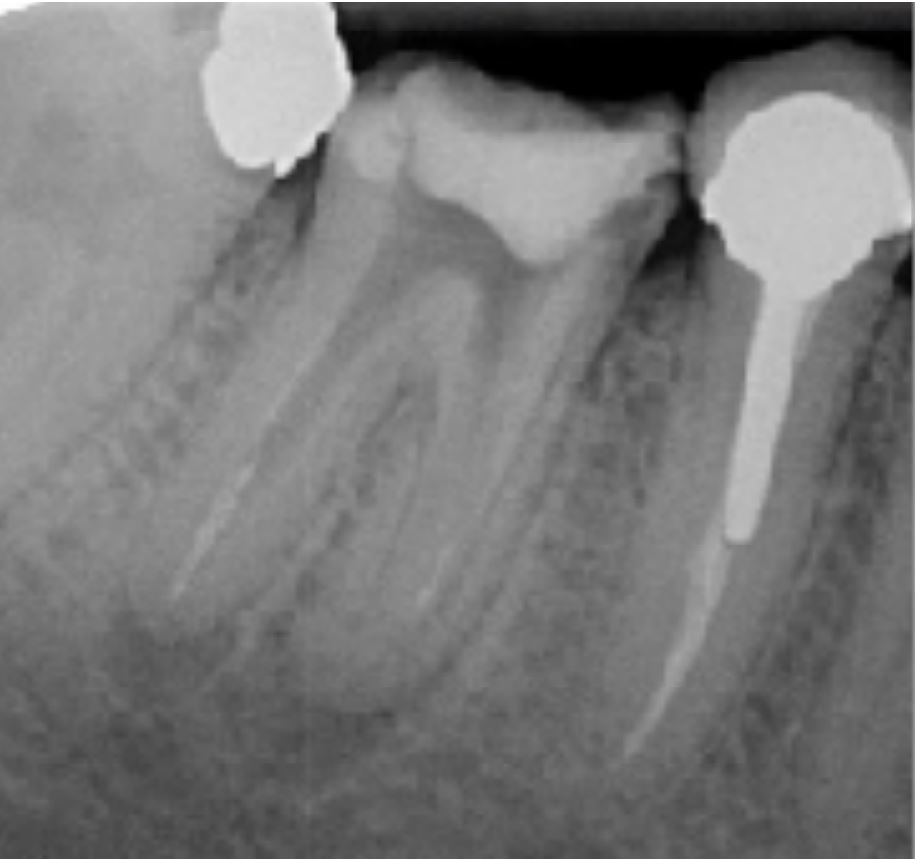

"Retraitement de 46"

Radio Per-Opératoire

Désobturation progressive du système canalaire à l'aide de séquence FANTA RETREATMENT

Mise en évidence d'un fragment instrumental dans la racine MV de la 46